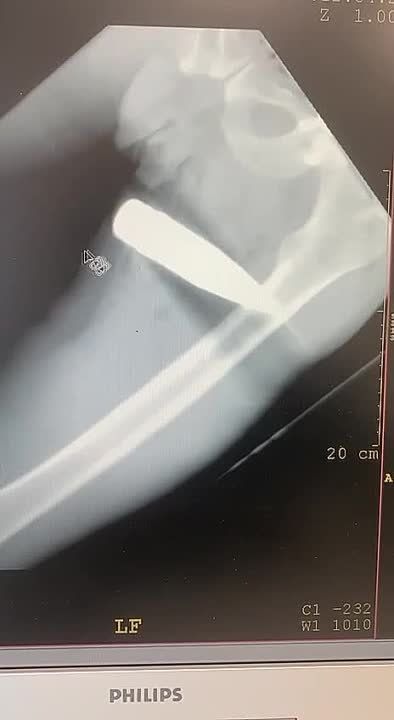

Помогаем нашимДрузья, медикам на бахмутском направлении срочно нужны медизделия для правильного и быстрого сращивания костей наших получивших серьезные ранения защитников. Это сложные конструкции, благодаря которым удается не...